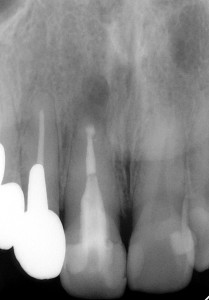

手術前 手術後 手術後1年

確かにしっかり治ってくれています。患者さんも喜んでくれています。